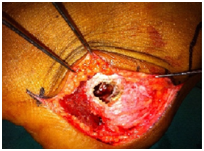

Under spinal anaesthesia, lateral expansile incision made and lytic cavity approached through a cortical window. Fibro-fatty tissue was curetted from the lesion. Erosion of the medial wall was noticed intraoperatively. After the thorough curettage cavity was filled with auto graft. Histopathological examination was suggestive of lipoma. Ankle was immobilised for two weeks and weight bearing started after six weeks. At six months of follow up lytic lesion healed with consolidation of the graft. At one year patient is walking with full weight bearing without pain and restriction of movements.

Intraosseous lipomas are diagnosed with plain radiography and CT scan (Figure 1) (Figure 2A) (Figure 2B). Mainstay of treatment is conservative; however surgery is indicated in severe pain not responding to conservative treatment, impending pathological fracture and malignant transformation (Figure 3). Treatment for these tumors is curettage and bone grafting (Figure 4) with good prognosis.8–10

Figure 3 Intraop Clinical photo.